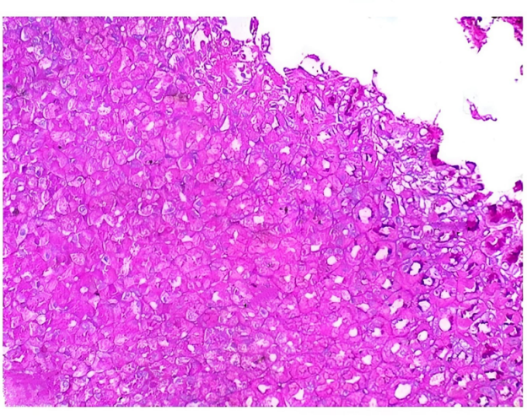

5. Test Group 3 / Standard Treatment (Near-Complete Healing)

The Test Group 3 tissue displays nearly complete mucosal restoration, with a fully continuous epithelial layer and well-formed, uniform villi similar to healthy tissue. Inflammatory cells are virtually absent from the submucosa, confirming the resolution of inflammation. A higher number of goblet cells indicates robust mucus production and restored mucosal defense. The submucosa appears normal, without signs of edema or fibrosis, demonstrating complete tissue remodeling. Overall, this group represents near-complete healing of the ulcerated mucosa.

Figure 11: Test Group 3